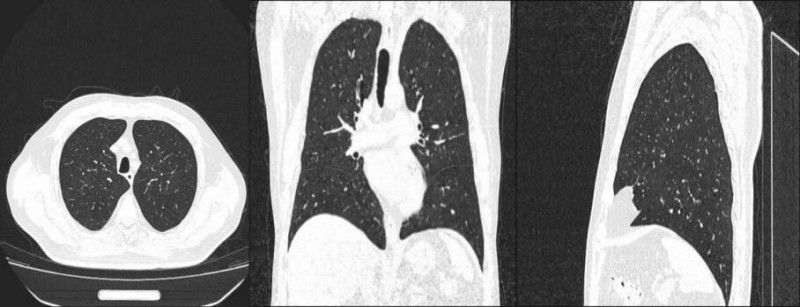

“孩子在外地不想让他们担心,以前单位体检要回大连,嫌麻烦就一直没查。”68岁的邱先生在外地工作多年,今年6月12日,他回到大连之后,在大连爱康卓悦体检中心完成搁置已久的体检,CT结果显示“右肺中叶17x15mm磨玻璃结节,边缘有分叶”。

经验丰富的放射科医生立即电话通知本人及家属,发送CT图像与初步报告,还叮嘱家属这是早期肺癌,建议去胸外科会诊微创治疗。后续在体检中心帮助下,邱先生于7月25日在某三甲医院手术,术后病理为微浸润性腺癌,无需化疗。康复后的邱先生逢人便说:“以前觉得体检是麻烦事,现在才懂,它是给健康上的‘保险’。”

“之前在2家医院、1家体检中心都查出双肺多发磨玻璃结节,没太当回事。”今年6月,刘先生体检时,CT发现左肺上叶囊腔灶外侧缘有5.11mm磨玻璃结节。大连爱康卓悦体检中心的医生当场找到他提醒“这是个类型比较少见的肺癌”。

当月,刘先生去大连某三甲医院胸外科会诊,考虑为早癌,最后病理证实为微浸润性腺癌。“幸好这次医生及时提醒,没让小病灶拖成大问题。”